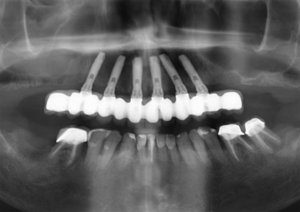

Figura 2 – Prótese protocolo superior fixa em seis implantes tipo hexágono externo (Implaci De Bortoli, São Paulo/Brasil) e manutenção dos dentes remanescentes inferiores. Os dentes 14, 13 e 23 foram extraídos, apesar da boa condição, para viabilizarem a colocação dos implantes superiores no planejamento para uma prótese fixa tipo protocolo.